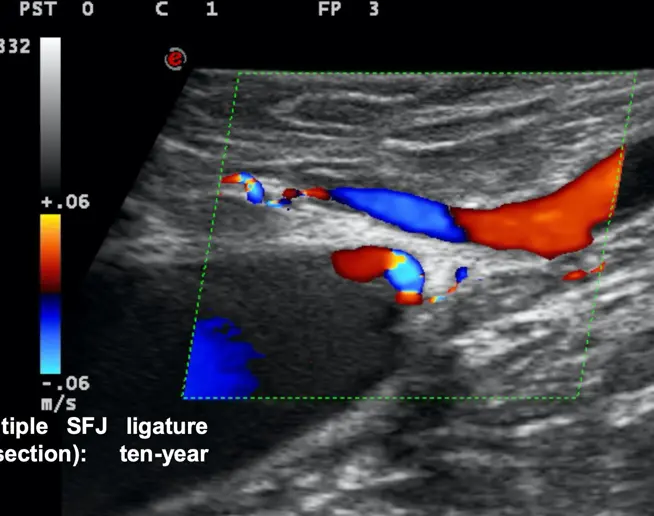

Un siglo más tarde, Claude Franceschi retomó el enfoque hemodinámico y desarrolló conceptos complementarios gracias a la investigación vascular mediante ecografía Doppler, de la que fue pionero y sobre la que publicó el primer libro en 1977, así como el primer libro sobre imágenes por ecografía vascular en 1986. Estudió la mecánica de fluidos para comprender sus observaciones y luego propuso un modelo hemodinámico de la fisiopatología venosa.

Procedimientos mínimamente invasivos con anestesia local y marcaje cutáneo previo en modo B.